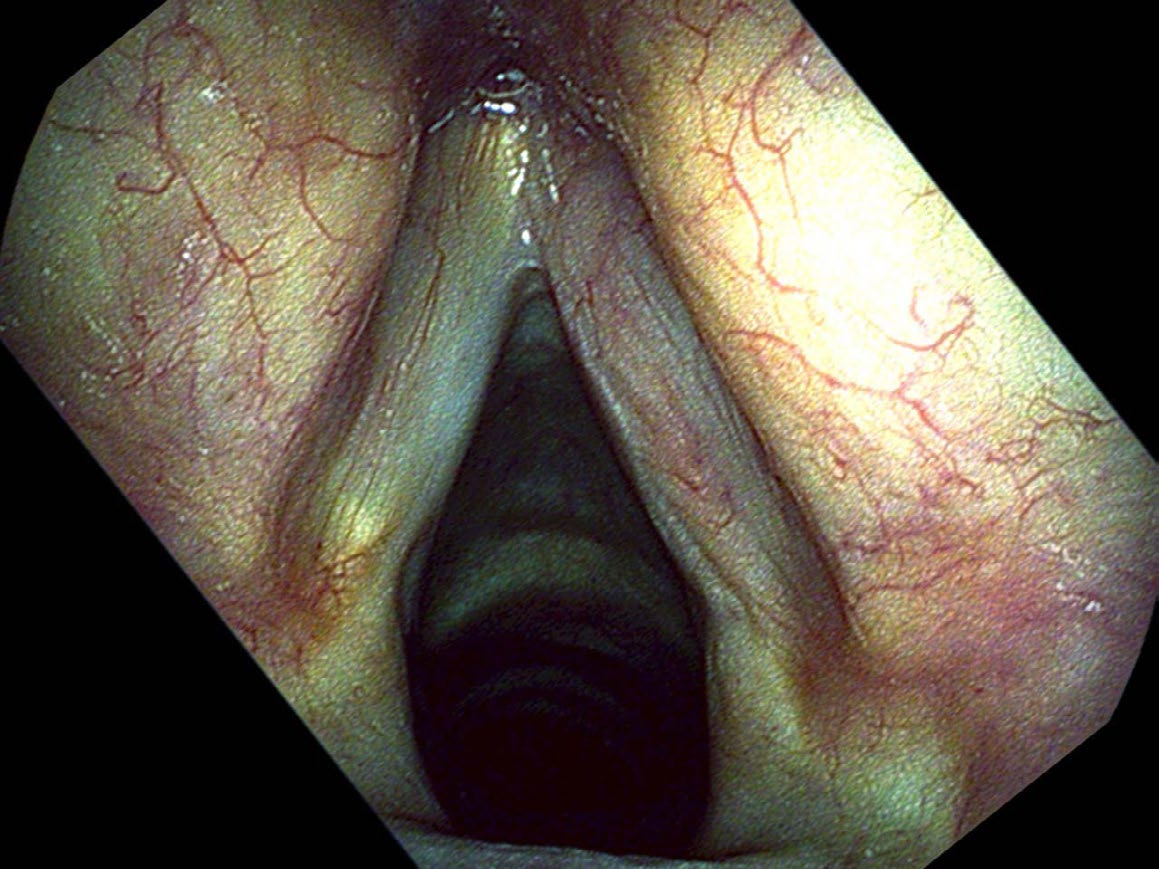

Despite its rather extensive appearance, this cancer proved to be entirely on the surface and was peeled off of the right vocal cord with a CO₂ laser. One month after the surgery he still had a slightly elevated red area on the edge of the vocal cord. While this appeared to be a granuloma on my endoscopic examination, Mr. Kowal now had an elevated concern for any finding that might represent cancer. Since lesions with blood in them respond well to the office pulsed KTP laser, we treated this and the red lumps were gone by his next office visit.

He returns to the clinic for frequent check-ups and the tumor has not recurred as of writing. Follow-up examinations are important in any patient with cancer. Because of the fear that the word cancer strikes in patients and physicians, there is a tendency to overtreat. Removing Mr. Kowal’s entire larynx with a total laryngectomy would have been equally effective treatment — more certainly it would have removed all of the cancer. However he would now be functioning without a voice box. When I removed Mr. Kowal’s tumor, I cut right on the interface of the tumor and his normal tissue. With regular, close examinations and with high-quality endoscopes, I believe that I will see any remnants or recurrences of the cancer early and can treat them appropriately while still very small.

This avoids the problem of surgical over-treatment that otherwise removes some normal vocal cord and makes the patient’s voice worse. It also avoids the problem of over-treatment with radiation therapy and chemotherapy. While radiation therapy is just as successful at treating small vocal cord cancers, normal tissue is exposed to the radiation and complications, such as a dry throat, are unnecessary and lifelong.

- Follow-up endoscopy is as important as the surgery itself: early detection of any recurrence allows targeted re-treatment without sacrificing additional vocal cord tissue.